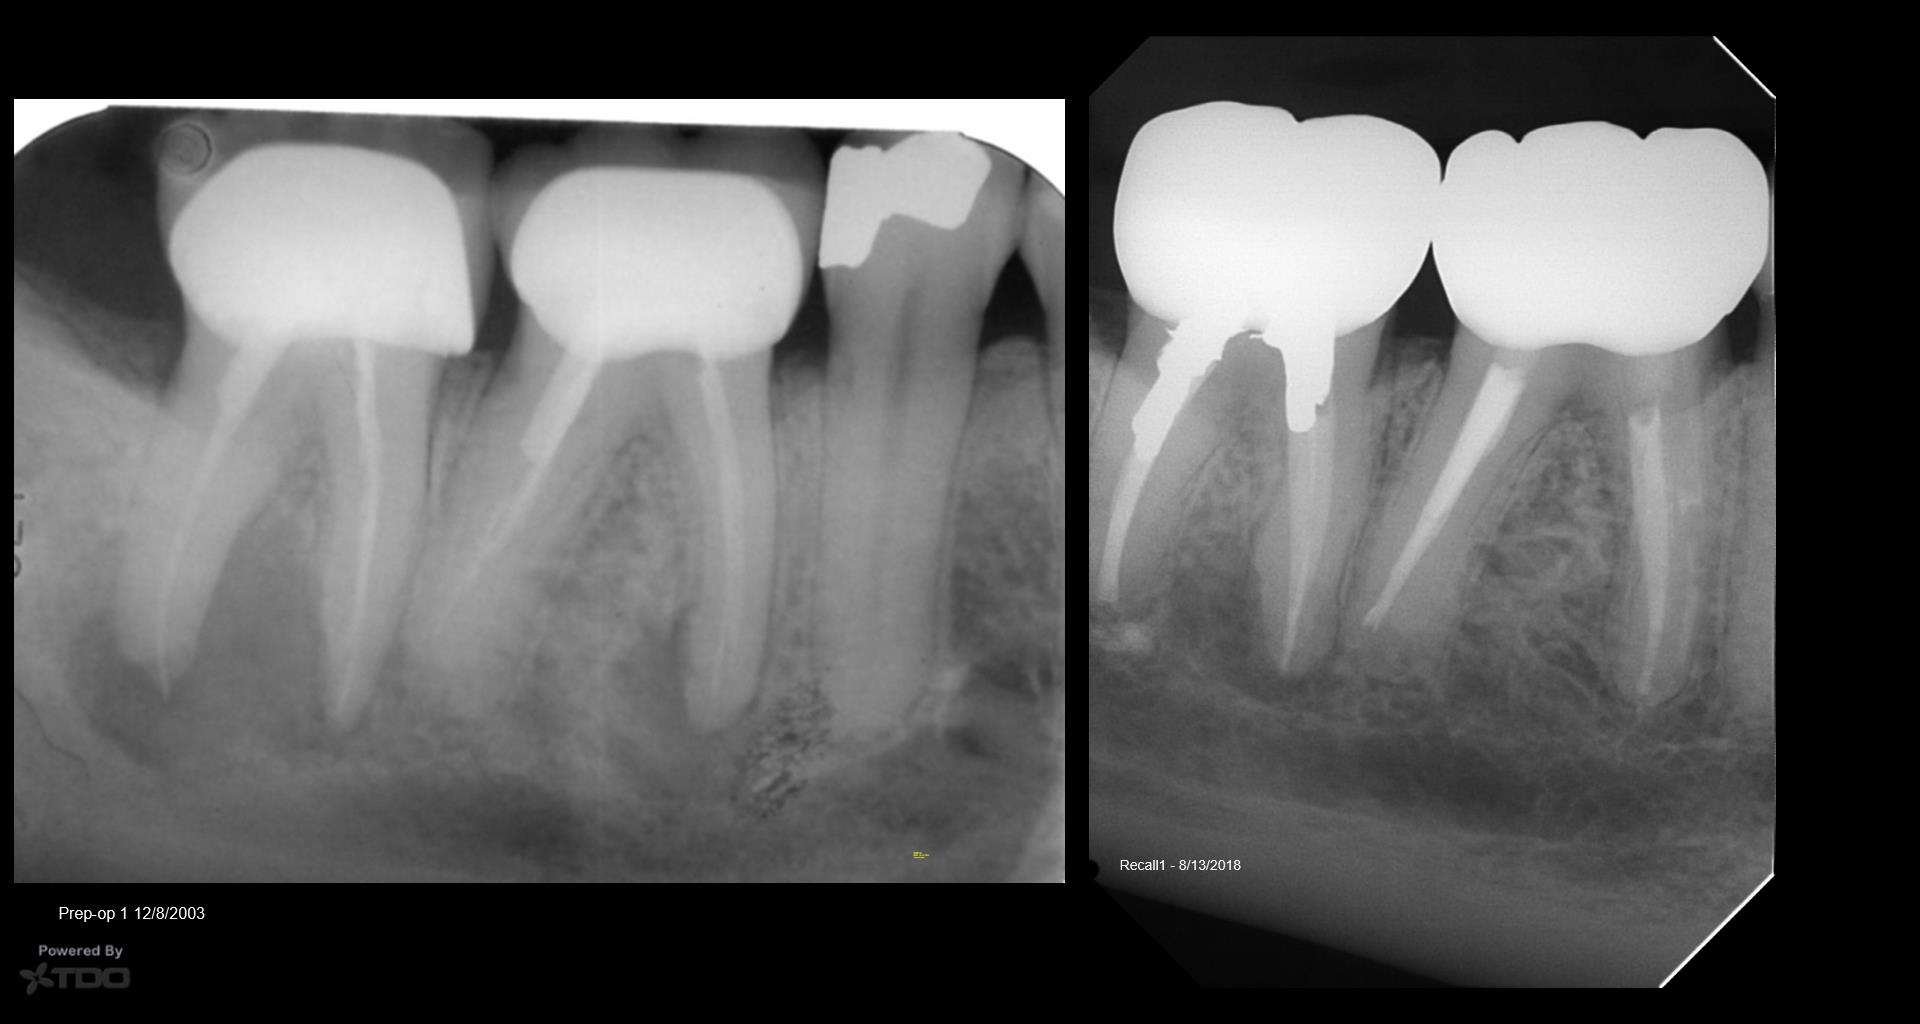

Very compliant patient—always made his recalls. Tooth has been asymptomatic for 15 years…and the periapical area had cleared—-now tender to biting and patient has an ache….No evidence of any occlusal issues. Will start the retreatment…again. Ugh….. gbc